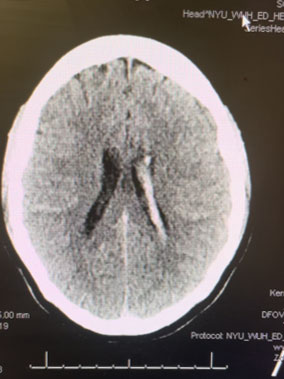

Head CT was consistent with a small acute left intraventricular hemorrhage (Figure 1).

Fig. 1